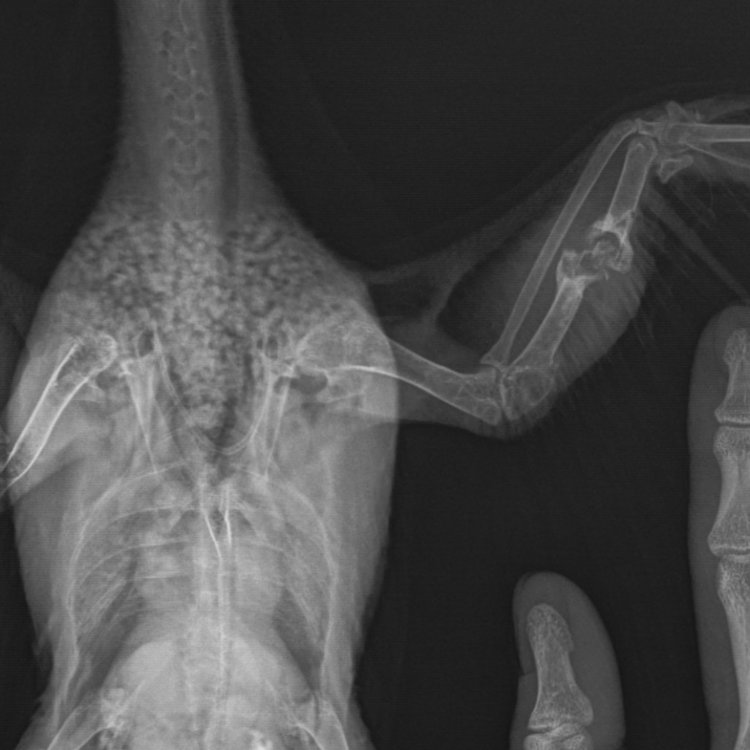

Штольц Опубликовано 15 июня, 2021 Автор #67 Опубликовано 15 июня, 2021 (изменено) Были у врача. Перелом без фиксации. Крыло опущено из-за воспалительного процесса в суставе. Сдали микроскопию помёта. Есть грибы, есть глисты. Причиной перелома, считают инфекционное поражение кости, но это одна из их предположений. Назначена терапия и противовоспалительная, и обесболивающая, и антимикотическая. Для поддержки хочу Карсил давать. Если не будет сложно: подскажите дозировку. У птеня нет аппетита. @маленький принц Для поддержки хочу Карсил давать. Если не будет сложно: подскажите дозировку. У птеня нет аппетита. Назначили гепатовет. Но дома есть составляющие этого препарата. Может, возможно их дать? Изменено 15 июня, 2021 пользователем Штольц

маленький принц Опубликовано 15 июня, 2021 #69 Опубликовано 15 июня, 2021 после какого препарата вытошнило? 55 минут назад, Штольц сказал: Для поддержки хочу Карсил давать. Если не будет сложно: подскажите дозировку. по пол таблетки смыв оболочку дважды в день 6 часов назад, Штольц сказал: Стресс. Ведь в клетке, хоть и в безопасности поставьте ему в клетке коробку в качестве домика чтобы мог прятаться и успокаиваться 5 минут назад, Штольц сказал: @маленький принц Вот дала все препараты. Прошел час. Голубя вытошнило. Что делать? перечислите что дали и в какой дозировке а сейчас дайте сорбент (уголь, энтеросгель, смекту итп) фото рвоты? 58 минут назад, Штольц сказал: Были у врача. Перелом без фиксации. Крыло опущено из-за воспалительного процесса в суставе. Сдали микроскопию помёта. Есть грибы, есть глисты. покажите анализы рентген делали? фото сустава размочив и раздвинув перья чтобы была видна кожа?

Штольц Опубликовано 30 июля, 2021 Автор #86 Опубликовано 30 июля, 2021 Друзья, я в замешательстве! Необходима ваша помощь в решении, что предпринять. Прошло 1,5 месяца с момента лечения. Перелом не затягивается. Три недели назад меняли схему лечения. Но, боюсь угробить птицу. Вчера сделали рентген, микроскопию помета и анализ сдали на бакпосев, так как дрожжи присутствуют в умеренном количестве, капиллярии есть и палочковая микрофлора. До этого лечили линкомицином, тербинафином, гепатоветом. В первичной схеме был синулокс, байтрил, тербинафин, флуконазол, дирофен, карсил. После первой схемы спустя три недели начала образовываться костная мозоль, схему поменяли, отменив синулокс, байтрил, флуконазол, назначили линкомицин, терфинафин. Сейчас отменили линкомицин, оставили гепатовет и терфинафин, и дирофен в схеме на три приёма. Сказали, что ждёт ампутация крыла. Что делать? Если есть дрожжевые грибы в умеренном количестве, то, может, необходимо поменять антимикотик? Добавить что-то для флоры? Даю гепатовет. Птица активна, но самостоятельно не ест - однозначный признак нездоровья. Ждём результат посева на микрофлору. Помёт имеет оформленность, но много влаги. Пока ждём результатов, чем помочь птице восстановиться. Верю в то, что ампутацию делать не будем, хочу верить, можно от неправильного лечения всю птицу искромсать... @OFA @маленький принц если есть возможность, помогите! @Welli @рябчик

маленький принц Опубликовано 30 июля, 2021 #90 Опубликовано 30 июля, 2021 11 часов назад, Штольц сказал: Сказали, что ждёт ампутация крыла. с чего это?! покажите как там кожа крыла выглядит гангрены ведь нет? НИ В КОЕМ СЛУЧАЕ НЕ СОГЛАШАЙТЕСЬ на ампутацию 11 часов назад, Штольц сказал: После первой схемы спустя три недели начала образовываться костная мозоль так ведь значит начало срастаться!